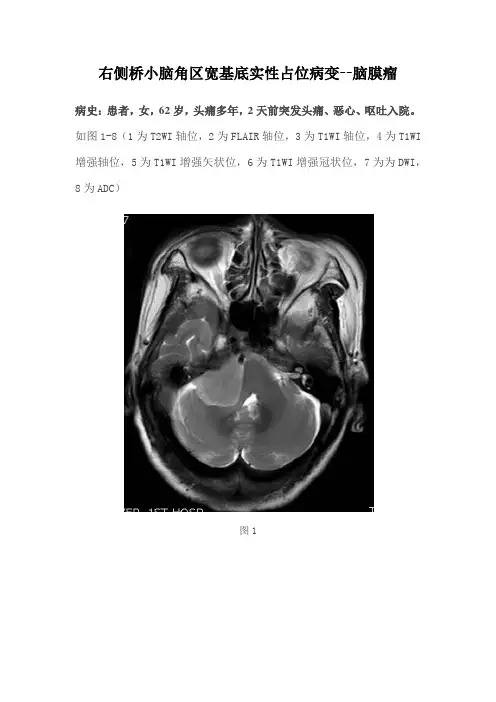

右侧桥小脑角区宽基底实性占位病变--脑膜瘤病史:患者,女,62岁,头痛多年,2天前突发头痛、恶心、呕吐入院。

如图1-8(1为T2WI轴位,2为FLAIR轴位,3为T1WI轴位,4为T1WI 增强轴位,5为T1WI增强矢状位,6为T1WI增强冠状位,7为为DWI,8为ADC)图1图2图3图4图5图6图7图8 基础影像解剖:图9图10图9-10为所示病例同层面轴位及矢状位正常T2WI图片,黄色箭头所示为正常耳蜗长T2信号,棕色箭头所示为正常听神经稍长T2信号,MRI图像中骨质因不含自由水呈低信号,无法显示内听道骨质结构,蓝色箭头所示为桥小脑角池长T2信号,其内无异常信号影,其内线形低信号为听神经及小血管流空信号影。

图1图2图3图4图5图6图7图8图1-8所示见右侧内听道正常(蓝色箭头),右侧桥小脑角区见宽基底实性异常信号影,冠矢状位可见病灶紧贴颅底,呈长T1稍长T2信号(黄色箭头),FLAIR呈稍高信号,增强呈轻度强化,可见脑膜尾征。

DWI呈高信号,ADC低信号。

右侧小脑半球及第四脑室受压变形。

影像描述:双侧内听道未见增宽或变窄。

右侧桥小脑角区见宽基底实性异常信号影,病灶紧贴颅底,信号均匀,呈长T1稍长T2信号,FLAIR 呈稍高信号,增强呈轻度强化,可见脑膜尾征。

病灶DWI呈高信号,ADC 低信号。

右侧小脑半球及第四脑室受压略移位。

影像诊断:右侧桥小脑角区占位病变,考虑脑膜瘤。